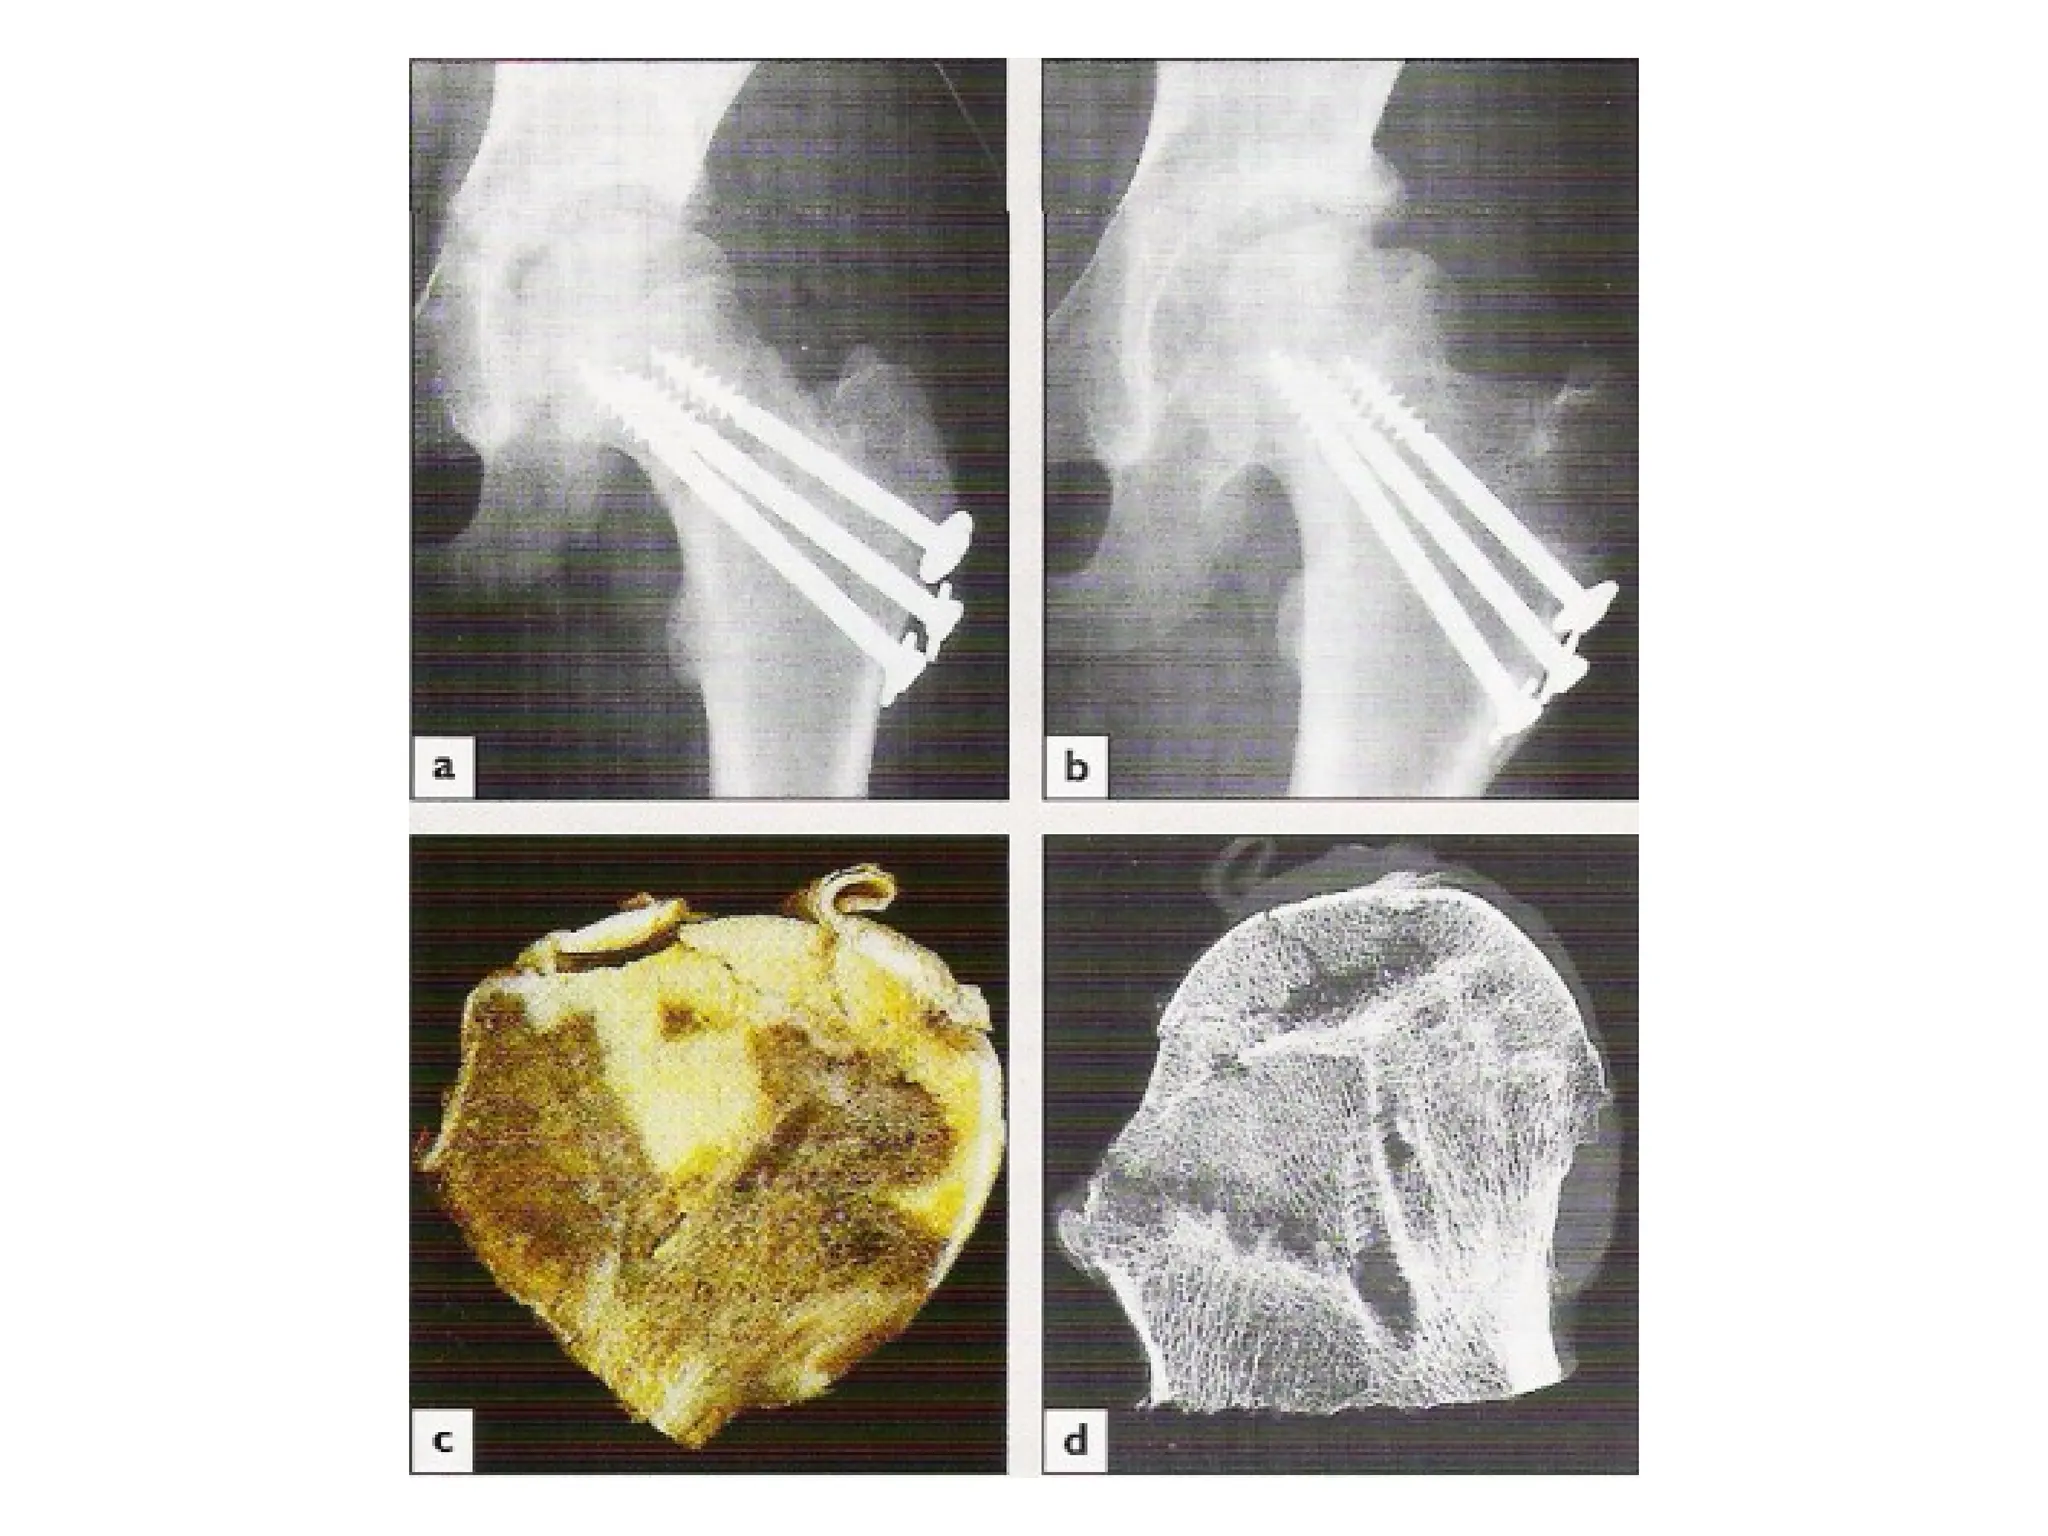

2-Fixation:

• The fracture is held with cannulated or a sliding screw and

a side-plate which attaches to the femoral shaft.

• Lateral incision is used

• Avascular necrosis (AVN):

• Necrosis of the femoral head:

-Displaced # 30%

-Undisplaced # 10%

• Occurs early at the time of injury, but the presentation is

late

• Collapse of the femoral head will cause pain and

progressive loss of function whether the # unites or not

• X-ray changes may not become apparent for months or

even years

• By using a nanocolloid scan, diminished vascularity may be

shown few weeks after injury